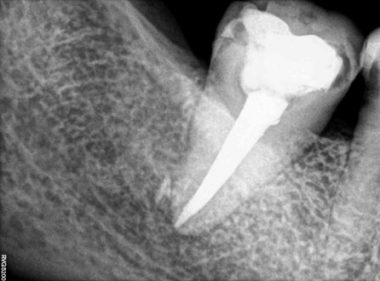

Patient Name:Rakesh Sinha

Tooth Involved :46

Diagnosis :Distocclusal Caries Involving Enamel And Dentin

Treatment :Indirect Restoration With Cuspal Coverage Of Distocclusal Cusp